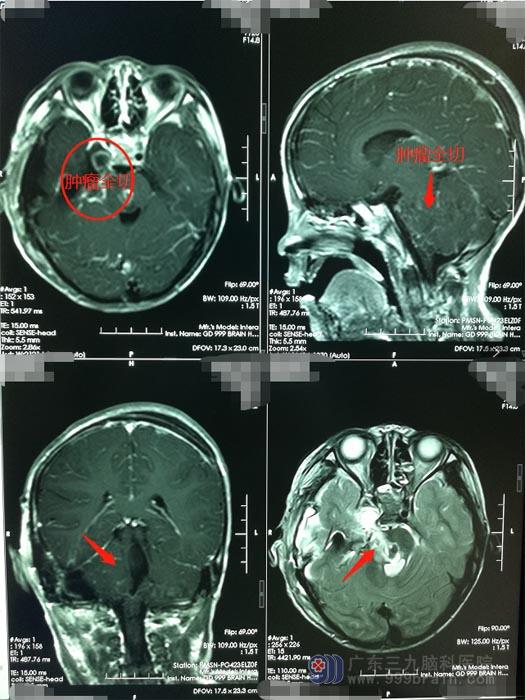

在广东三九脑科医院进一步影像检查后,诊断:右侧中后颅窝巨大三叉神经鞘瘤。

完善术前检查后,鲁明带领神经外五科治疗团队在全麻下为小萱行“右侧中后颅窝巨大三叉神经鞘瘤切除术”。术中见肿瘤起源并明显压迫三叉神经,将肿瘤顺利全切,面听神经、后组神经等保护良好,Labble静脉等引流静脉保护良好。